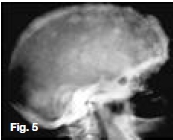

Figures 1, 2, & 3 show a mixed radiolucent/opaque lesion affecting the maxilla, crossing the midline in an edentulous patient, causing flattening of the palate. A lateral skull radiograph of another patient (Fig. 4) shows osteoporosis imperfecta in the posterior and anterior parts of the skull (green arrows) along with thickening of the calvarium and cranial vault which are cardinal radiological signs of the condition. Figures 5 & 6 illustrate "cotton wool" radio-opacities in the skull and the base of the skull shows dense sclerosis. All the images mentioned so far are typical features of Paget's disease. Sir James Paget, surgeon and pathologist who is best remembered for naming Paget's disease. The disease is idiopathic and can be divided into three stages: initial bone resorptive phase, vascular phase with osteoblastic repair, and approximal/ sclerosing phase. The jaws are involved in approximately one in Ave cases, with the maxilla being affected about twice as frequently as the mandible. During the initial phase of bone resorption, the affected bones may be deformed or painful, particularly the weight-bearing structures such as the long bones of the legs (Fig. 7A & B). Later the affected bones expand, commonly in the maxilla, mandible or cranium. At this stage, the dental patient who wears full dentures may complain that the fit of the dentures is becoming progressively poorer. When the maxilla is affected, the alveolar ridge widens and the palatal vault can flatten (Fig. 2). When teeth are present, they may become increasingly spaced, with extensive jaw enlargement. Neurologic complaints can result from increased deposition of bone in the areas of the foramina of the skull causing headaches, auditory disorders progressing to deafness, visual disorders progressing to blindness, facial paresis, and vertigo. The bones are relatively brittle; hence, fractures are likely. Generalised radiolucency/osteoporosis intermediate stage with mixed radiolucency/radiopacity, "driven snow" coarse trabeculation, "cotton wool" radio-opacities in the final stage (Figs. 5 & 6). Hypercementosis, loss of lamina dura, obliteration of the periodontal ligament spaces (Fig. 8) and external root resorption (Fig. 9) may also be present. The upper hand wrist radiograph (Fig.10) of another patient shows the disease affecting the phalanx of the third digit.